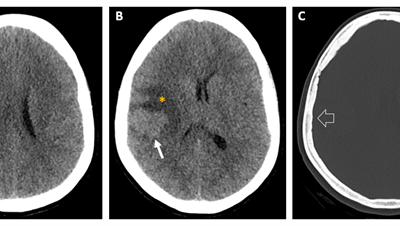

Caso del mes Enero 2026

« Todos los casosAutores Javier Pardo Maiza, Joan Carreres Polo, David Castro Vidal, Pablo García...